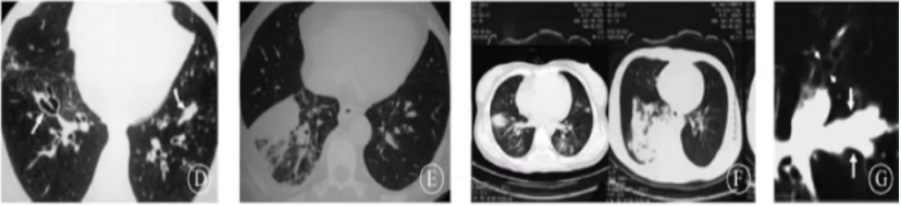

粒缺患者常见晕轮征、楔形改变和空气新月征等特异性改变(图2),非粒缺患者常见实变、结节、空洞、树芽征、中央型支气管扩张等非特异性改变(图3)

图片

3  非粒缺IPA患者影像学表现

粒缺与非粒缺患者IPA影像学改变的差异与发病机制不同有关。对于免疫功能缺陷(例如粒缺)患者,曲霉为所欲为,在肺部的各个部位发起进攻,破坏肺组织;气道壁增厚,或引起大片实变小的气腔结节、树芽征、腺泡结节,也可以融合成团;血管受累,主要是血管炎、出血、栓塞、坏死,表现为晕轮征、空气新月征、楔形实变。而在免疫功能正常患者中,曲霉感染比较局限,很少发展壮大,曲霉只能寻找肺部薄弱之处攻击,首先攻击残存的空洞或空腔,也就是我们常见的曲霉球或CPA。此外,在免疫功能亢进患者中,免疫系统对曲霉的敏感性极高,曲霉一旦进入气道内就会立刻被发现,在大气道内筑起强大的防护屏障,仅在大气道内引起病变和相应的反应,多为曲霉引起的免疫反应改变。